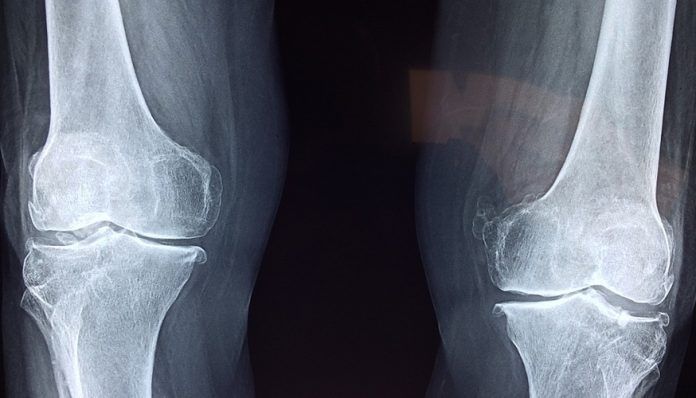

Un problema de los que son prácticamente irreversibles en salud, es la degeneración del cartílago. Cuando esto sucede, y el material de colágeno comienza a degradarse en las articulaciones de las personas, comienzan los problemas de movilidad. Existen casos tan severos, que la persona no consigue solución más que la intervención quirúrgica. Ahora este panorama podría estar a punto de cambiar gracias a BioPen.

Gracias al BioPen, los expertos son capaces de introducir dentro de la articulación afectada una mezcla efectiva para estimular la regeneración del cartílago. Este gel del que se hacen cargo para el tratamiento se compone de células madre mesenquimales que provienen del tejido adiposo del humano. Lo conocido como la grasa de manera popular. Las mismas están cargadas de metacrilato de gelatina, así como otros hidrogeles de ácido hialurónico metacrilato.

La receta forma un gel que puede reemplazar el cartílago desgastado de los pacientes. El BioPen facilita su penetración hacia la zona anatómica específica, valiéndose de moldes a la medida exacta para el intervenido. Una vez se ha inyectado el gel, se procede a utilizar luz ultravioleta sobre ella para generar fotopolimerización.